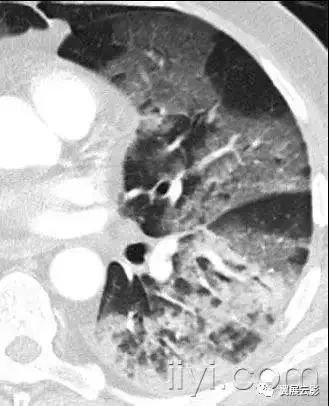

十九、肺实变:

平片和CT:肺实变表现为肺实质密度的均匀一致性增高,导致肺血管和气道壁边缘不清。有时可见含气支气管征。只有在极少数的情况下,肺实变的密度变化有助于鉴别诊断,例如脂性肺炎是密度减低,胺碘酮中毒时密度增高。

图示为多灶性的肺实变。